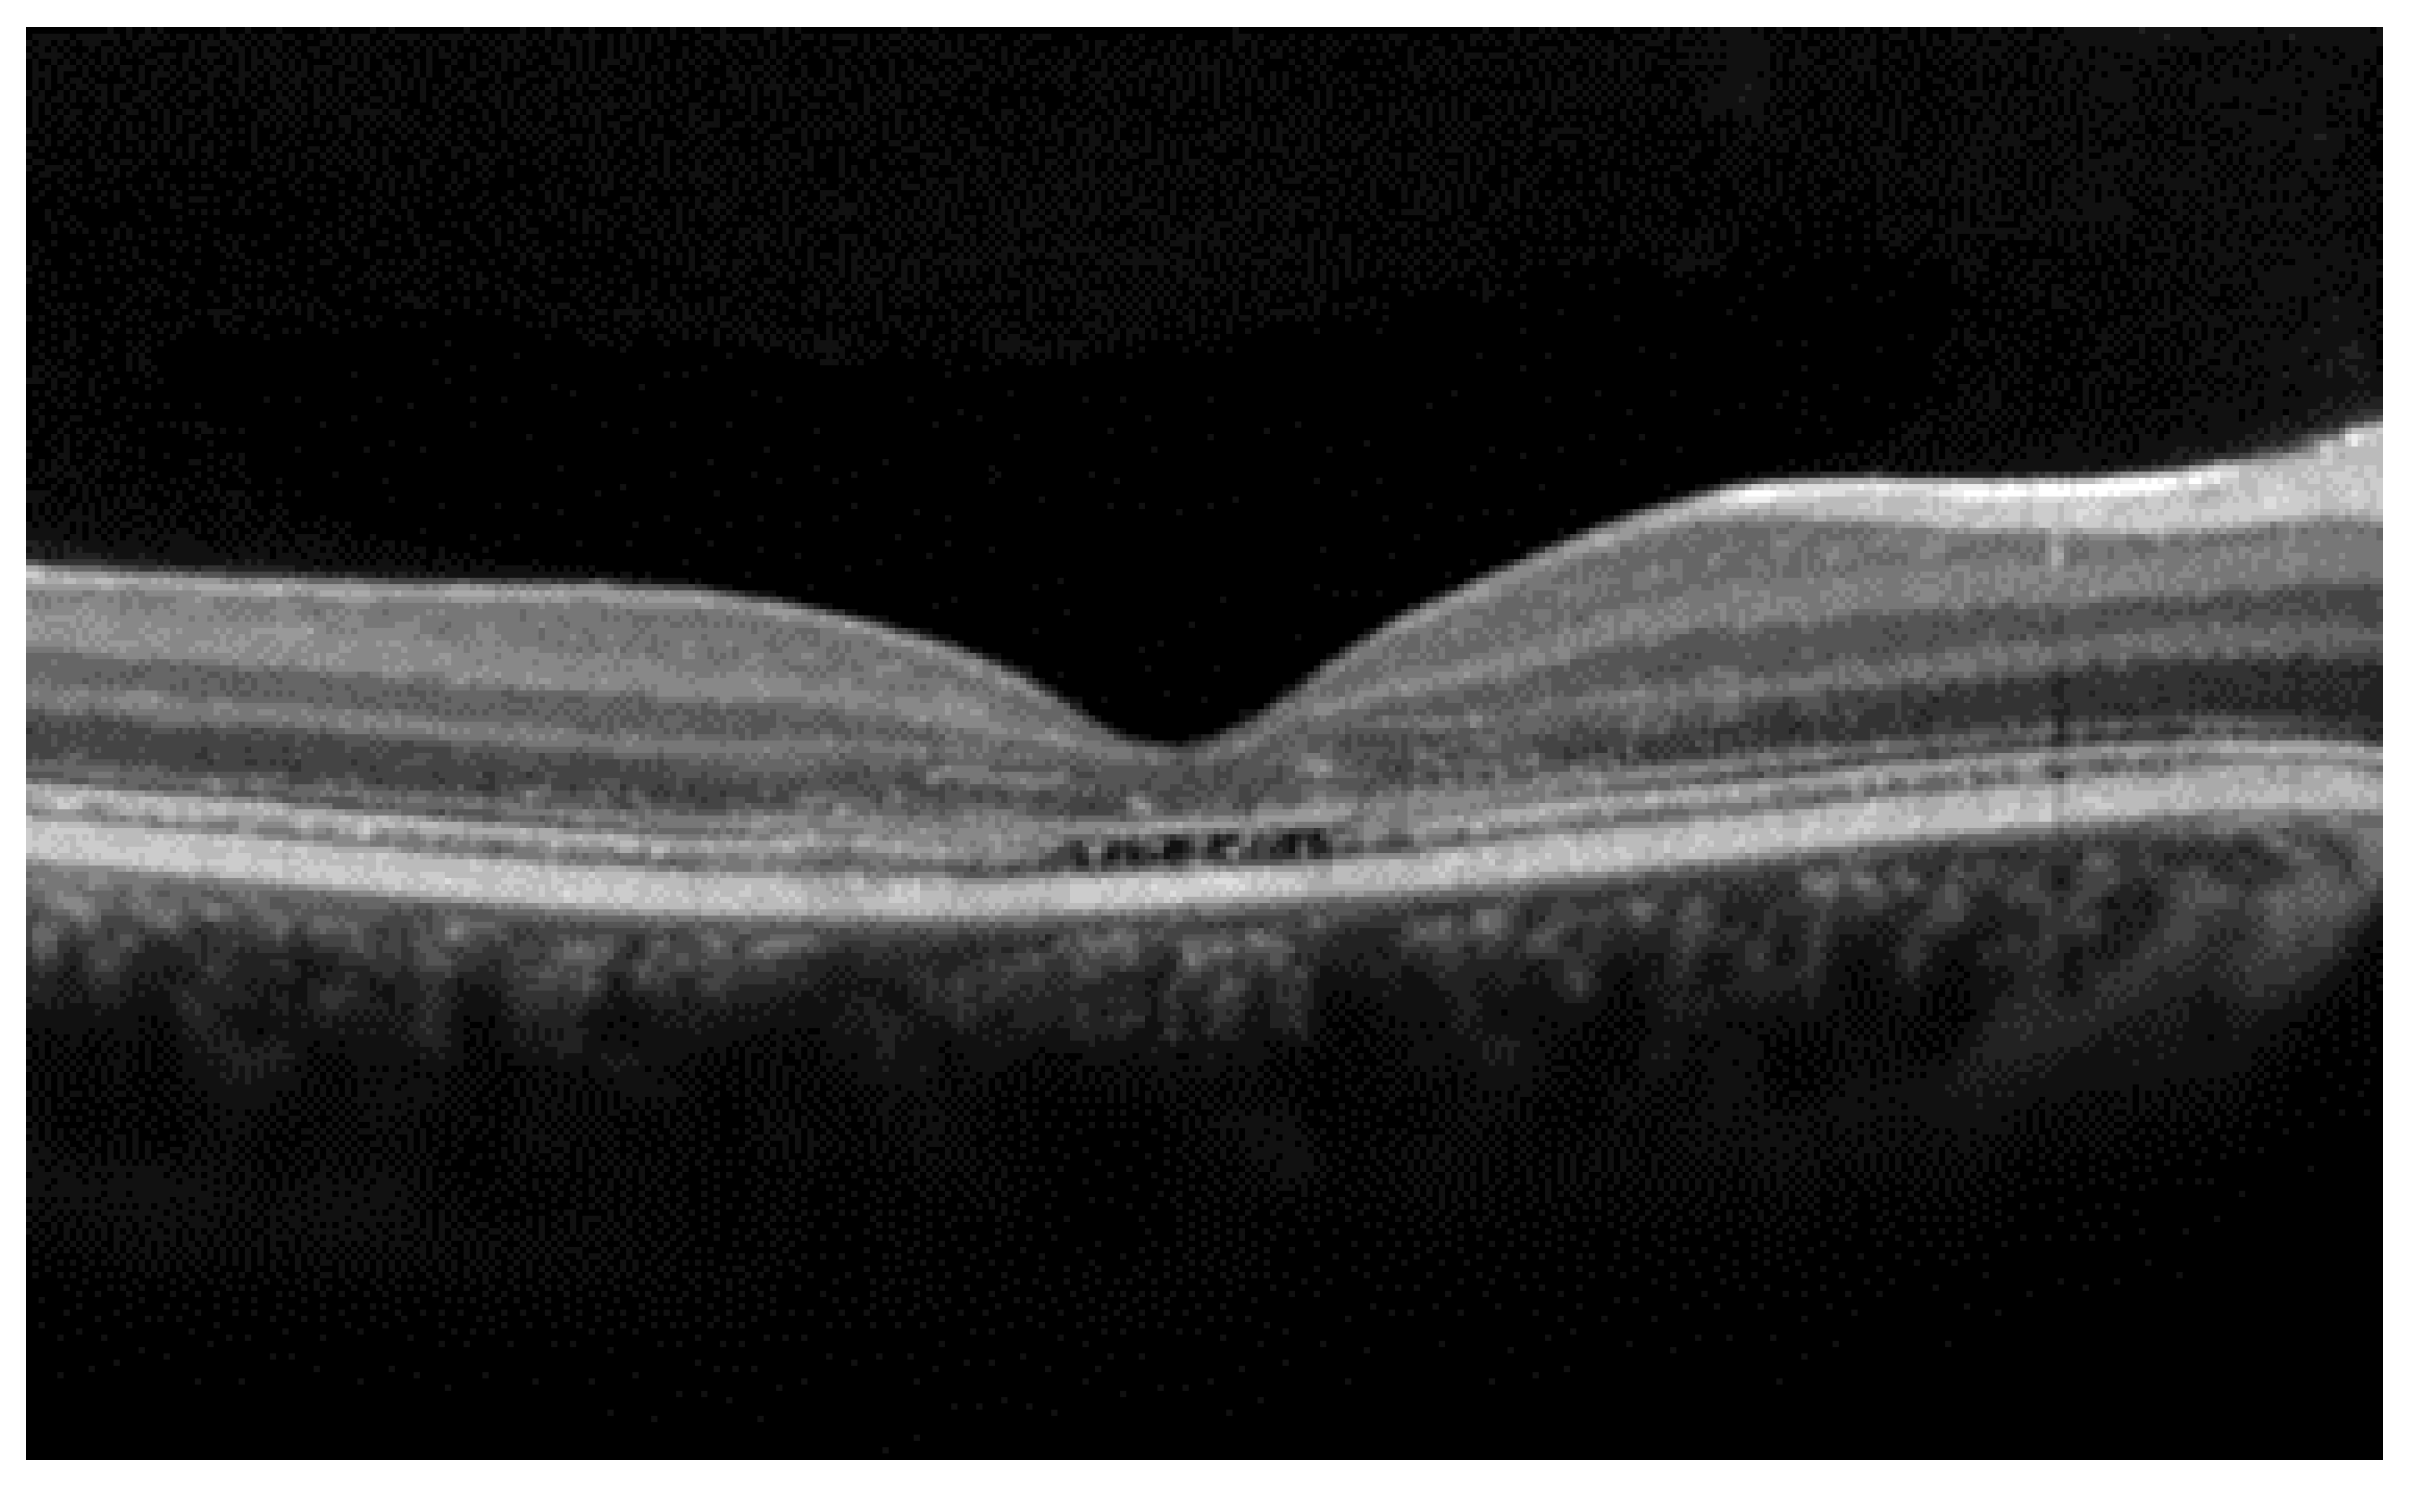

2. Stargardt Disease

| Stargardt disease |

|